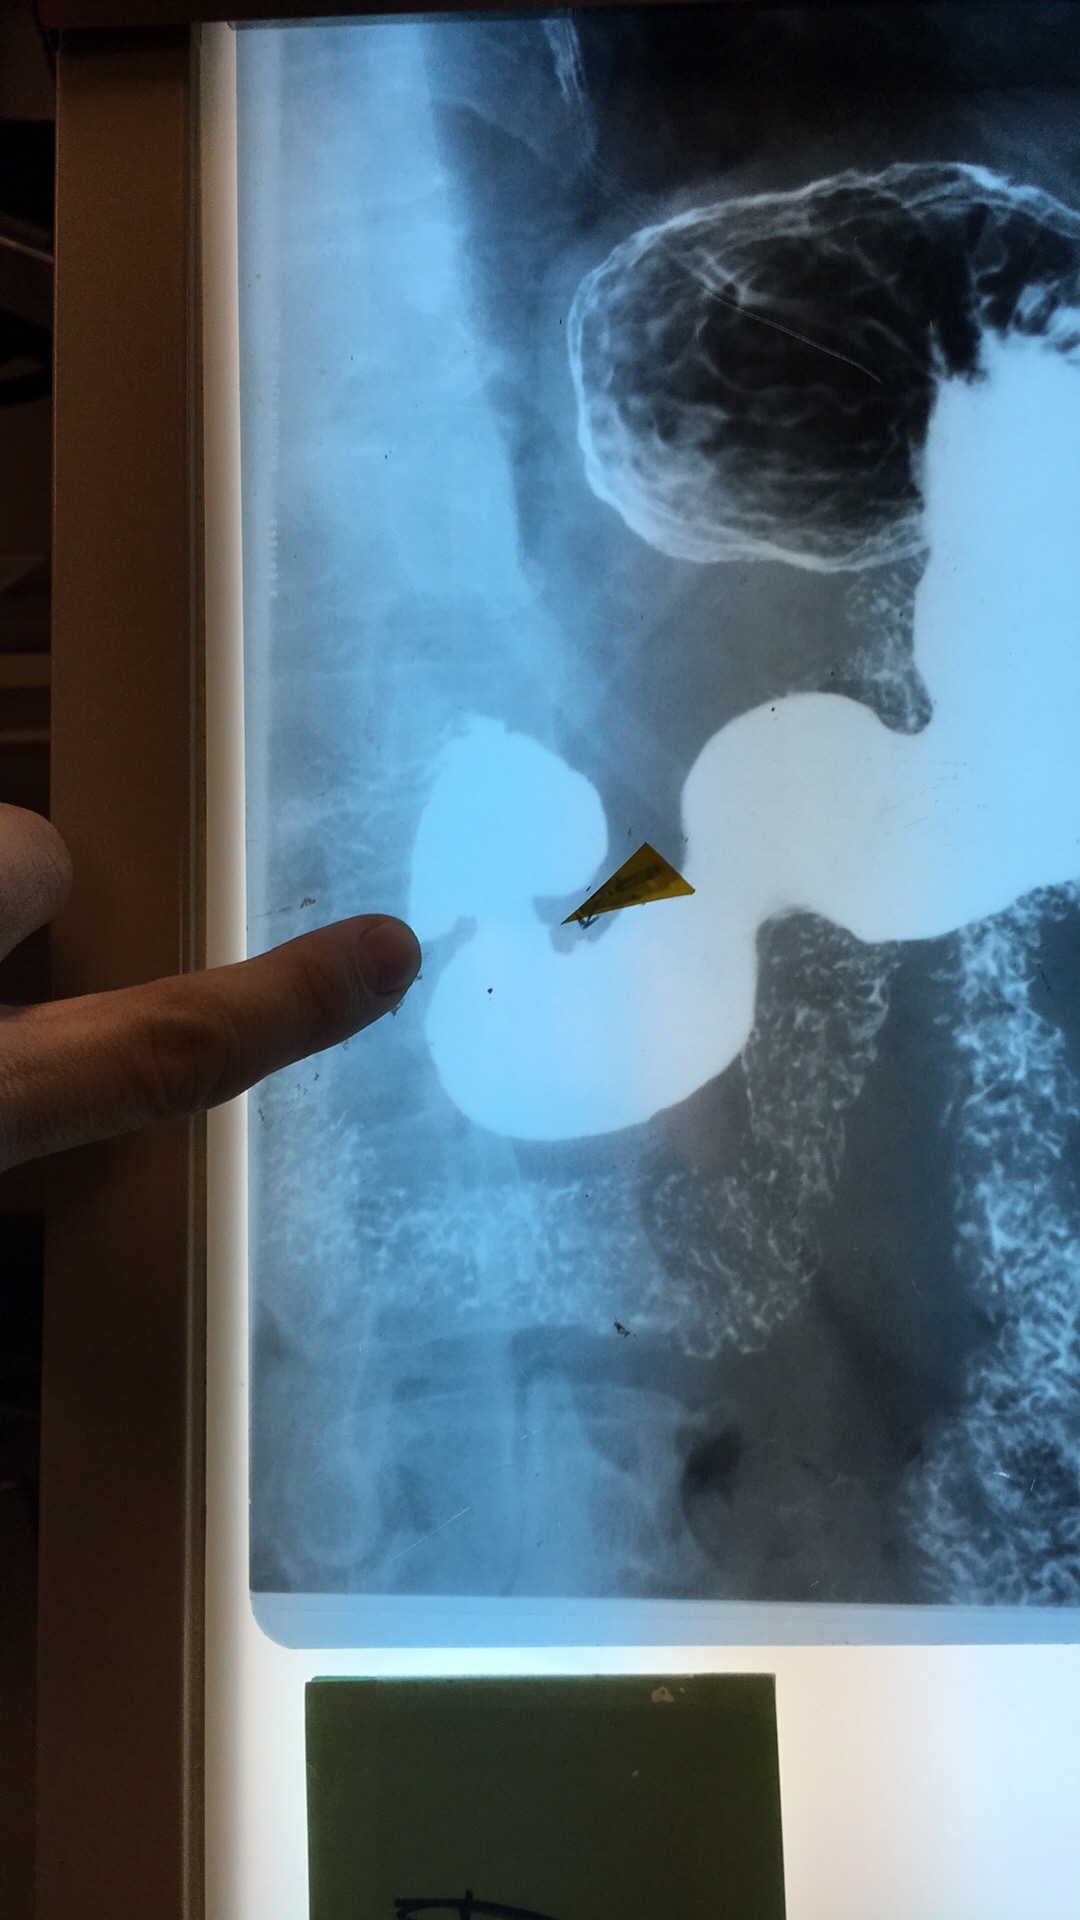

What and where? What goes through?

Renal Pelvis. Urine goes through to ureter.